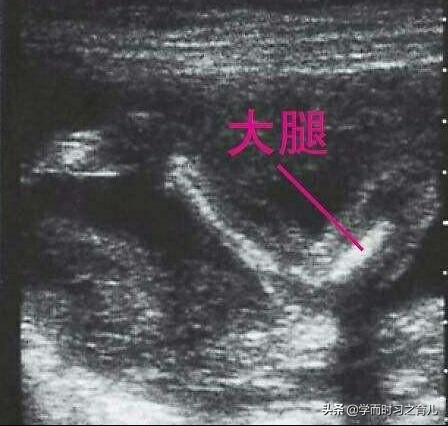

相信有不少准妈妈都碰到过这样的情况,其实胎儿腿短一般是指宝宝股骨长偏短。股骨是胎儿的大腿骨,那股骨长顾名思义就是宝宝大腿的长度。

通过B超测量胎儿股骨长,有时可能会存在比较大的误差,当然了,存在这种误差一般跟很多因素有关,比如B超师的经验和水平,再比如宝宝的姿势和体位(一般怀孕晚期胎儿较大,宝宝只能双腿蜷曲在准妈妈的子宫内)等等。